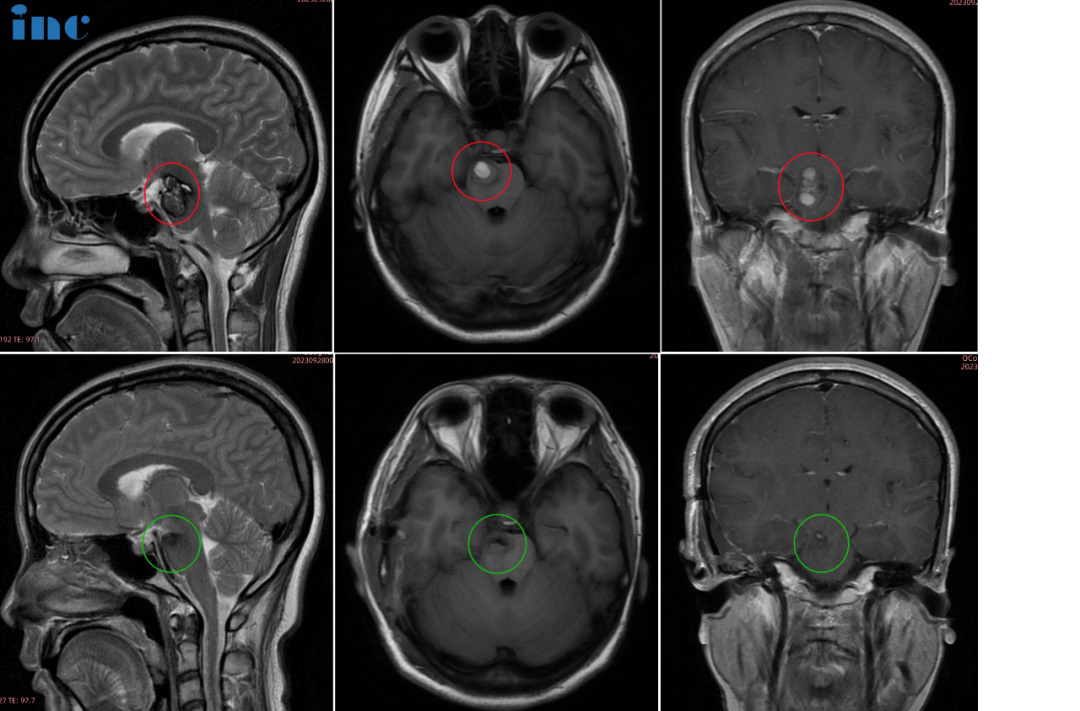

30岁的萱萱2023年3月查出中脑及桥脑右侧占位海绵状血管瘤继发出血。当地医生考虑手术风险大,偏瘫几率大,建议保守治疗。和很多年轻的脑干海绵状血管瘤女性患者一样,步入婚姻的...

30岁的萱萱2023年3月查出中脑及桥脑右侧占位海绵状血管瘤继发出血。当地医生考虑手术风险大,偏瘫几率大,建议保守治疗。和很多年轻的脑干海绵状血管瘤女性患者一样,步入婚姻的她迎接新的小生命。但又怕脑干海绵状血管瘤万一出现急性脑干出血,致患者和胎儿于困境中,又该怎么办?

9月27日,在苏州独墅湖医院,巴教授顺利全切手术,手术后无瘫痪、无视神经损伤、无呼吸控制和昏迷风险。术后当天巴教授前往ICU查房时,已拔除气管插管、已苏醒。萱萱感激说道:“I can see,I can feel,I can move,I have power。”术后一天查房时,萱萱激动地说:“That’s amazing,I feel normal,as the same as(I did the surgery before).So amazing.(这太神奇了,我感觉我和正常无异,和术前无症状时一模一样。太神奇了)”

术后4天查房,萱萱问能不能准备顺利备孕,巴教授告知萱萱脑干海绵状血管瘤已经全切了,备孕可以的。术后6天,萱萱下地行走自如。